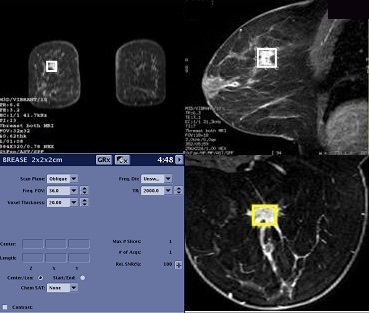

BREASE

About this task

Typically, BREASE is performed after first completing a study of the breast using VIBRANT. BREASE uses a TE-averaged, PRESS spectroscopy acquisition, compatible with the 4-, 7-, or 8-channel Breast coil.

Use these steps to acquire a BREASE spectrum for breast spectroscopy. The spectrum is displayed in the Viewer. MR breast spectroscopy can show if elevated concentrations of the Choline metabolite are present in a lesion.